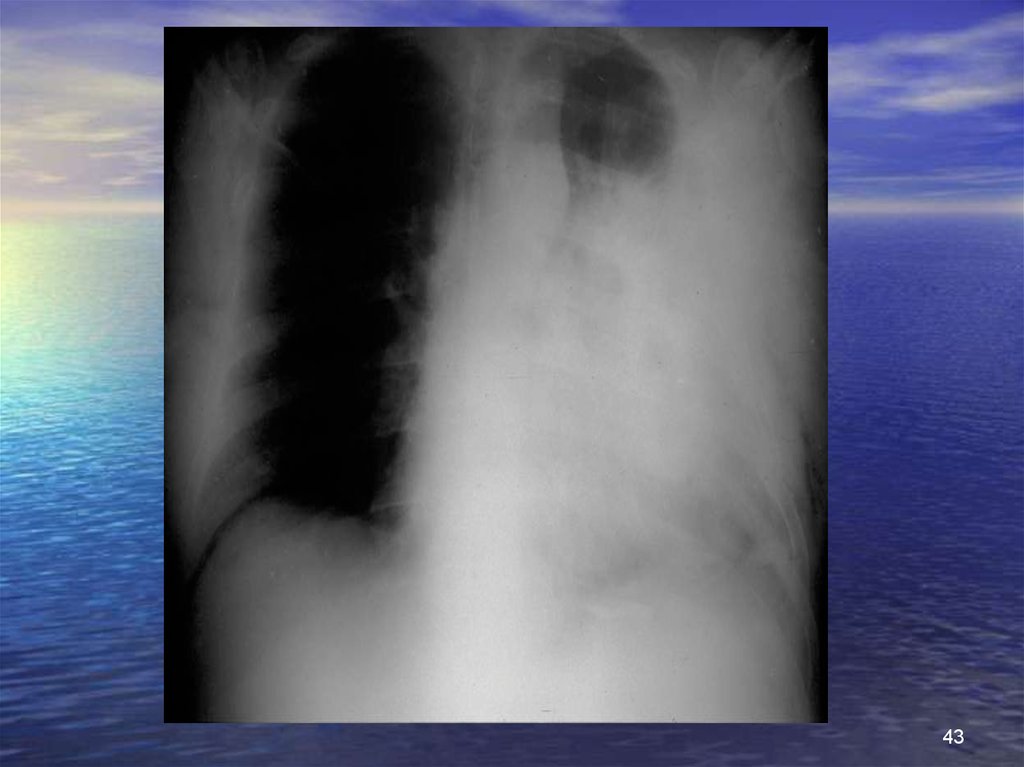

43.

43